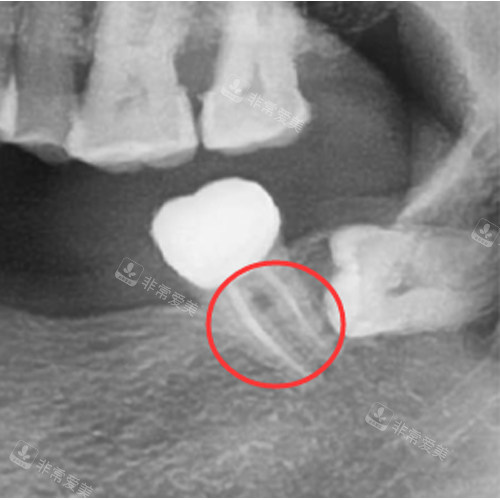

在设备方面,凯旋口腔引进了国内外较高的口腔诊疗设备,如智能化口腔全景机、激光治疗仪等,能够更精密地诊断病情,提高治疗结果。